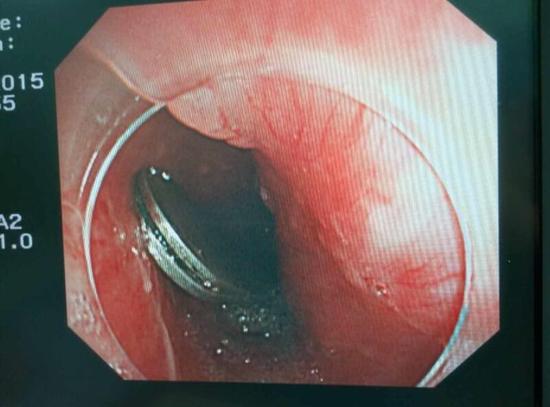

醫(yī)生從華先生胃里取出的鑷子和打火機(jī)

手術(shù)中,范醫(yī)生通過胃鏡準(zhǔn)確發(fā)現(xiàn)了胃里的鑷子。但讓他驚訝的是,在華先生胃底竟然還躺著三個(gè)被腐蝕了的打火機(jī),打火機(jī)的金屬部件都已經(jīng)不見了。

隨后,范醫(yī)生先用圈套器套取出了長10厘米的鑷子,再一個(gè)一個(gè)地取出了打火機(jī)。整個(gè)取出過程小心謹(jǐn)慎而又一氣呵成,只用了不到10分鐘。